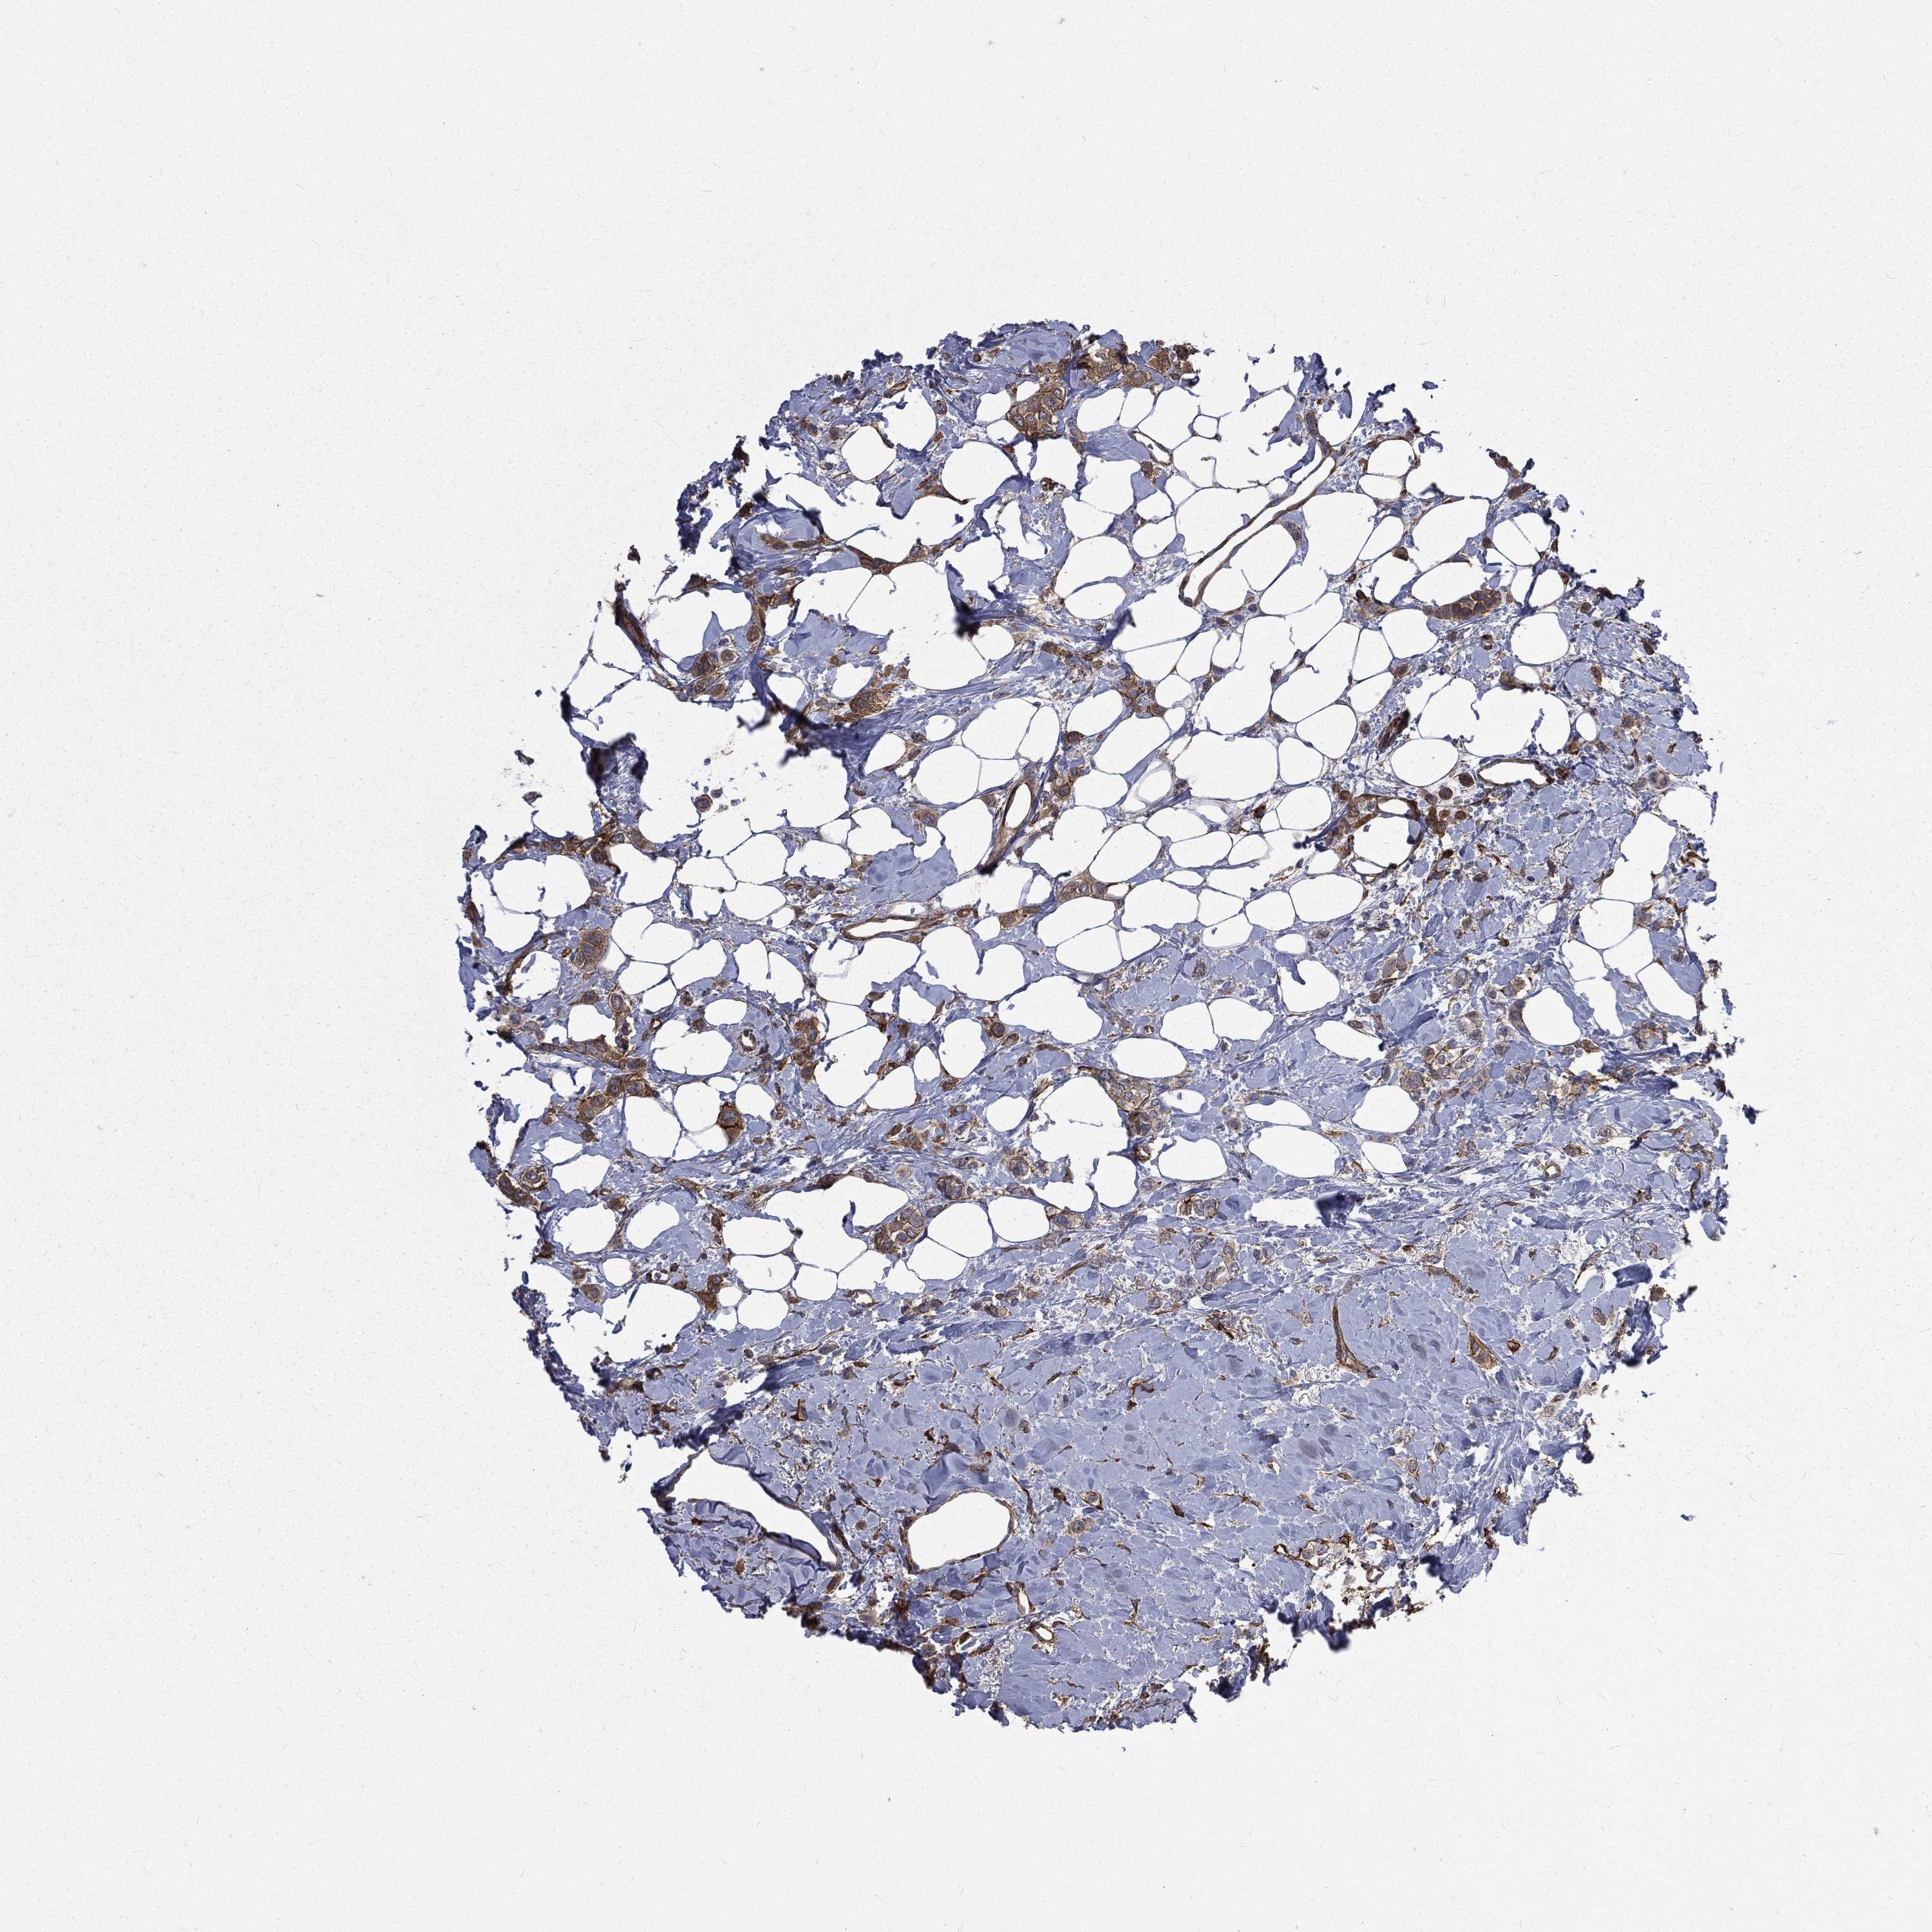

BRCA TCGA BRCA VALIDATION PROTEIN EXPRESSION

ANTIBODIES

AND

VALIDATION